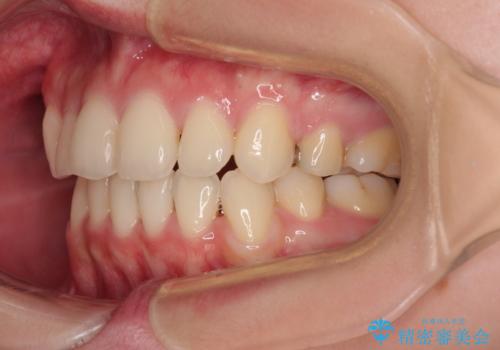

- 八重歯やクロスバイトを気にして来院された患者様です。

口元の突出感はありませんでしたが、デコボコが強く、非抜歯矯正とすると出っ歯仕上がりとなる可能性があったため、上下左右の第一小臼歯4本を抜歯し、ワイヤー装置にて矯正治療を行うこととしました。

デコボコがスッキリするだけでなく、口元の突出感も少し改善され、満足のいく仕上がりとなりました。